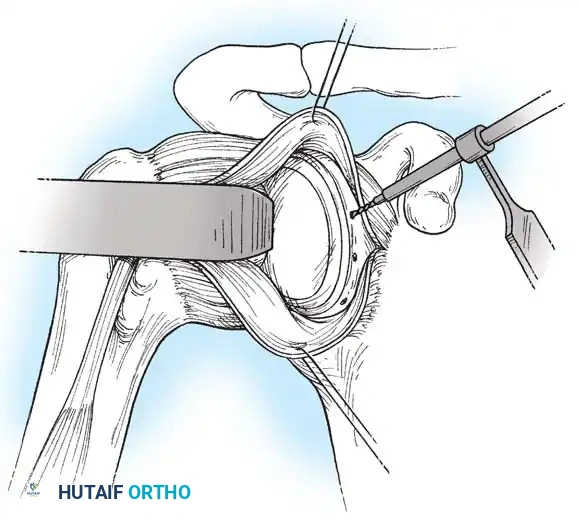

Capsulotomy and Joint Inspection

A vertical or T-shaped capsulotomy is performed based on the degree of capsular laxity and the planned shift.

- For a standard Bankart repair with an inferior capsular shift, a vertical incision is made 1 cm medial to the humeral articular margin. A horizontal limb can be added to create superior and inferior capsular flaps.

- Tagging sutures are placed in the capsular flaps for traction.

- A Fukuda retractor is placed within the joint to retract the humeral head laterally and posteriorly, exposing the anterior glenoid rim and labrum.